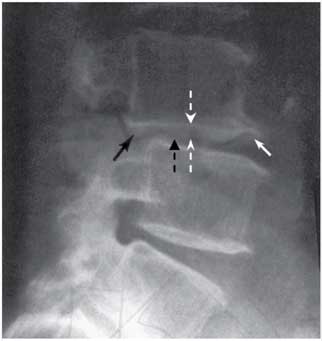

| 14:30, 14 августа 2017 | Bol spina15.jpg (файл) | 9 КБ | Рентгенография пояснично-крестцового отдела позвоночника пациента с хронической люмбалгией. | 1 | |